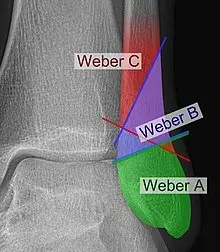

Type A Weber Ankle Fracture:

Type A fractures occur below the level of the ankle joint. These fractures involve the fibula and are typically stable, with minimal disruption to the ankle mortise (the joint formed by the tibia and talus). Treatment for type A fractures are usually conservative (physio and period of immobilisation).

Type B Weber Ankle Fracture:

Type B fractures occur at the level of the ankle joint itself. These fractures involve the fibula and may also involve the ligaments that stabilise the ankle joint. Type B fractures can be further subclassified as B1, B2, or B3, depending on the degree of ligamentous injury and joint instability.

Type C Weber Ankle Fracture:

Type C fractures occur above the level of the ankle joint. These fractures involve the fibula, but they also include a fracture of the tibia (the larger bone of the lower leg) or disruption of the syndesmosis, the ligamentous complex that connects the tibia and fibula. Type C fractures often require surgical intervention to restore the anatomical alignment of the bones and stabilize the joint.